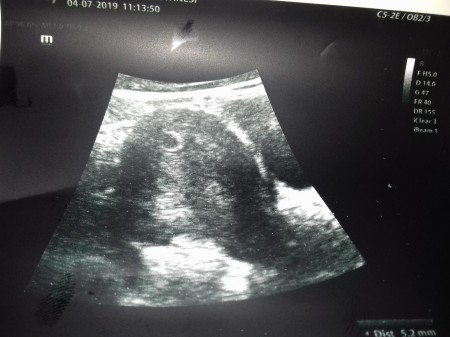

Merhaba arkadaşlar bugün randevum vardı gittim kese göründü 5.2 mm ama bebek ve kalp atışı daha görünmedi ayın 15 ine gel dedi ve sadece ulturasyonda baktı kan almadı hcg için ve kaç haftalik diye sormayı unutmusum .6+1 hamileyim son adet tarihine göre . Son adet tarihine gore doğrumudur

Bir sorum daha var kese hangisi nerde

Yukarda sol tarafta küçük yuvarlak birşey